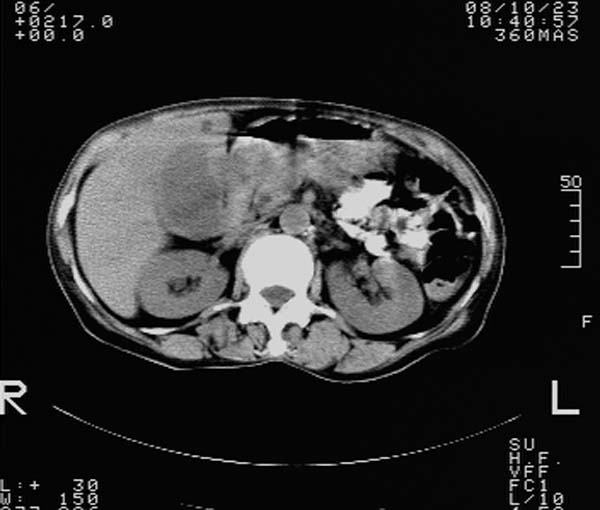

f,67y。反复右上腹痛。余无异常。

前五幅未服造影剂。后面图像有上传重复的。请战友们发表意见。

胆囊结石、胆囊癌伴邻近脏器受侵,不除外黄色肉芽肿性胆囊炎,建议增强扫描。肝多发囊性占位性病变,囊肿或囊性转移。

胆囊内结石,胆囊壁不规则增厚,胆囊胃窦区解剖结构欠清晰,楼主提示为少见病,考虑bouveret综合征?黄色肉芽肿性胆囊炎?肝内多发低密度占位,建议增强或b超